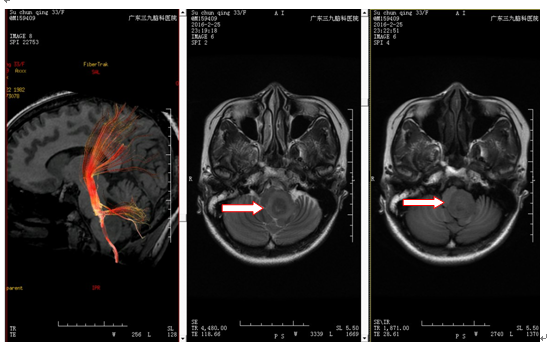

苏女士,33岁,因“头晕半年”入院。半年前无明显诱因出现头晕,程度中等,以头仰位后明显,无头痛、恶心、呕吐及肢体抽搐,由于不影响正常生活,一直未予特别处理,近期出现头晕较前略加重,遂到当地医院就诊,行头颅CT提示脑干占位性病变,未予处理。现为求进一步诊治,来我院就诊,门诊拟“枕骨大孔区占位性病变”收治入院。病后精神、睡眠良好,胃纳正常,大小便正常。头颅MR提示脑干占位性病变。

诊断:脑干占位性病变,考虑低级别胶质瘤可能性大

治疗:入院后完善术前准备,于2016-3-2行脑干占位性病变切除术,术中见脑干延髓区肿瘤,向左外侧生长,血供一般,边界欠清,大部分钙化明显。给予镜下大部分切除肿瘤,术后给予抗炎、营养神经等对症治疗,予预防感染、止血、营养神经等康复治疗,术后病理检查提示:毛细胞星形细胞瘤(WHOI级)。

脑干肿瘤早期一般不易被发现,尤其是低级别胶质瘤或海绵状血管瘤未出血时期,一般不引起脑干神经核团或颅神经功能损害表现,故大部分病人早期会被漏诊。一旦发现,最好手术治疗,以明确病理为主要目的,同时在术中电生理监测、术中导航引导下尽可能多切除肿瘤,注意操作仔细,避开颅神经、脑干神经核团,尽可能减少由于颅神经损害带来术后并发症。该病例主要特点为病变强化不明显,并且钙化为主,术前不存在明显颅神经损害症状,术中行肿瘤基本切除,术后患者恢复比较理想,病理提示I级胶质瘤,预后良好。